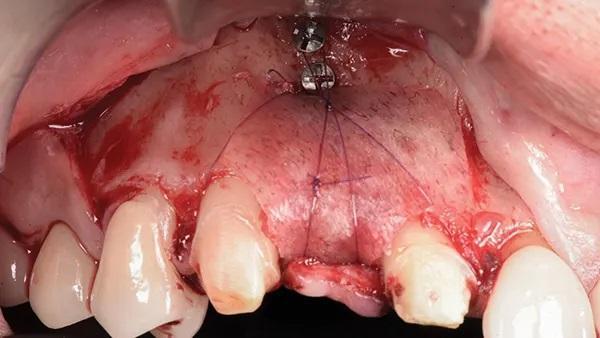

После установки анкерных микровинтов аутогенная кость соединяли с равным количеством 70:30 минерализованного/деминерализованного кортикального аллотрансплантата (OraGRAFT MD 70/30, Lifenet Health) и адаптировали к границам дефекта. Мембрану из сахарного сшитого коллагена (Ossix Plus, Datum Dental) помещали поверх дефекта, чтобы удержать костный трансплантат в этом месте. В этом случае использовались две мембраны: одна была адаптирована под буккальный угол окклюзионной линии, а вторая — под язычный угол окклюзионной линии. В это время рассасывающийся монофиламентный шов (Resorba Glycolon, RESORBA Medical GmbH) использовали для начала стабилизации, вводя его через язычный лоскут снаружи внутрь (от эпителия к надкостнице), на расстоянии 5-7 мм от десневого края, как было описано ранее. Затем этот шов располагают над медиальной стороной мембраны и закручивают вокруг наиболее переднего фиксирующего винта, снова накладывают на мембрану и выводят через язычный лоскут изнутри наружу (от надкостницы к эпителию) на 5-7 мм дистальнее первоначальной точки входа (Фото 5 и Фото 6).

После этого шов затянули. Следили за тем, чтобы проколы язычного лоскута располагались не менее чем в 7 мм от края лоскута, чтобы в итоге можно было провести двухслойное ушивание горизонтальным матрасным и одиночным прерывистым швами. Ту же процедуру повторили по всей длине дефекта, чтобы обеспечить достаточную стабилизацию мембраны над композитным костным трансплантатом. После завершения стабилизации выполнили двухслойное первичное ушивание (Фото 7). Этого удалось добиться, наложив два горизонтальных матрасных шва на расстоянии 7-10 мм друг от друга, чтобы уменьшить натяжение по краям лоскута и оттянуть его. Наконец, одинарные простые прерывистые швы равномерно распределили в 5 мм от края лоскута по всей длине лоскута.